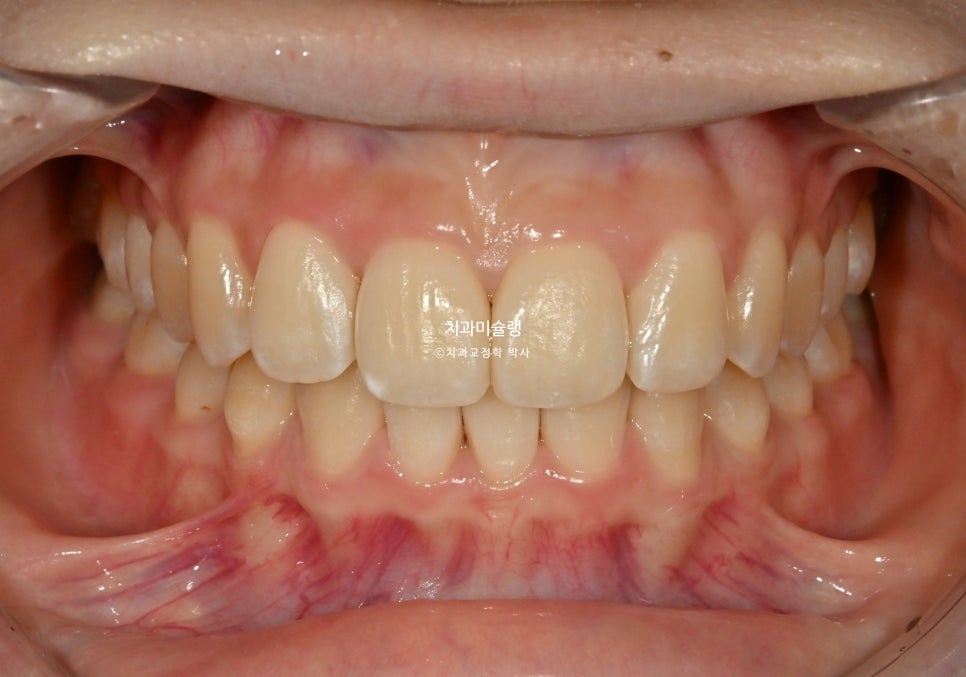

2026년 3월 – 치료 완료

11월부터 26년 3월까지, 13개 추가장치를 모두 낀후 치료를 마무리 했습니다.

총 치료기간은 1년, 재제작은 1회 했습니다.

이제 전후비교 볼게요.

2025.03-2026.03

깔끔해진 미소와 잘 유지된 입동굴

45도 측모 에서는 웃을때 약간의 돌출감은 여전히 남았으나 환자분은 만족하셨죠.

교정기간동안 치근흡수는 없으며 기울어져 있던 앞니 뿌리는 평행하게 재정렬되었습니다.

교정 전후 입매 변화는 없습니다.